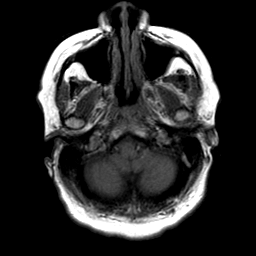

Cerebral hemorrhage, MR Study mr-t1 -- Slice #4

[Home][Help][Clinical] Slice 4